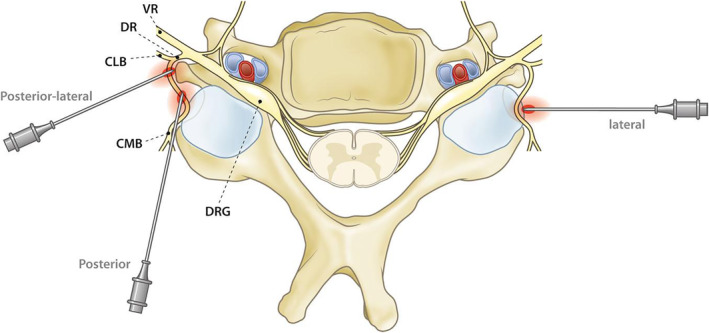

Abstract Image